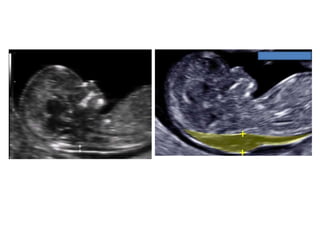

Amniotic band sequence:

Amniotic band sequence refers to a highly variable

spectrum of congenital anomalies that occur in

association with amniotic bands

Amniotic band sequence: Amnioticband sequence refers to a highly variable spectrum of congenital anomalies that occur in association with amniotic bands The estimated incidence of ABS ranges from 1:1200 to 1:15,000 in live births, and 1:70 in stillbirths

Anomalies include: Craniofacial abnormalities— eg, encephalocele, exencephaly, clefts, which are often in unusual locations; anencephaly. Body wall defects (especially if not in the midline), abdominal or thoracic contents may herniate through a body wall defect and into the amniotic cavity. Limb defects — constriction rings, amputation, syndactyly, clubfoot, hand deformities, lymphedema distal to a constriction ring. Visceral defects — eg, lung hypoplasia. Other — Autotransplanted tissue on skin tags, spinal defects, scoliosis, ambiguous genitalia, short umbilical cord due to restricted motion of the fetus